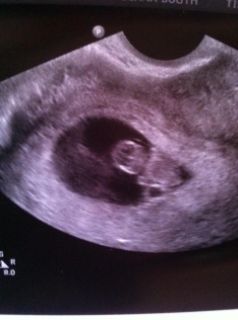

She turned the TV on and there he or she was, bobbing their little head from side to side and just perfect! It was the most amazing moment of both of our lives that's for sure. We could see the heartbeat beating away (173 bpm!!) and we were able to hear it. ![]()

The baby measured at 8w1d which I completely expected because I knew I had ovulated later. So the baby is right on track and she said everything looks perfect.

Here is our little pumpkin, due Oct. 30th!